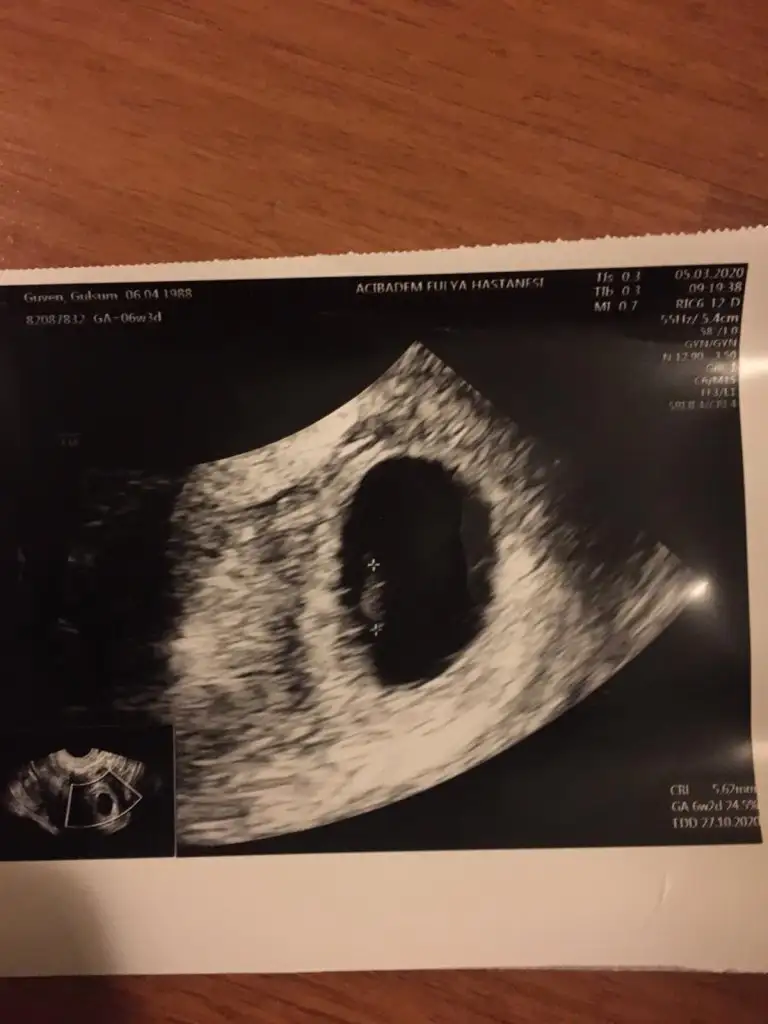

Merhabalar Ikra meyra Ikra meyra sizden rica etsem benim icinde tahminde bulunmaniz mumkunmu bugun gittim normalde sat a gore 8+4 ama doktorum 9+3 gorunuyor cok iyi dedi tahminde bulunabilirmisiniz😊